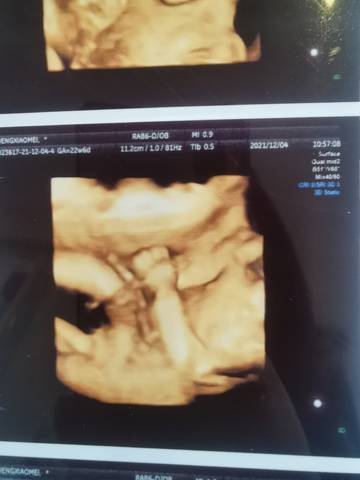

这张可以看出男孩女孩吗?

你好亲爱的,通过这个来判断男孩女孩是不太准确的哈。那么这个男孩女孩都是我们最爱的宝贝哈,我们要给他同等的关爱和呵护,也祝你可以如愿以偿,心想事成,祝你好运加油????